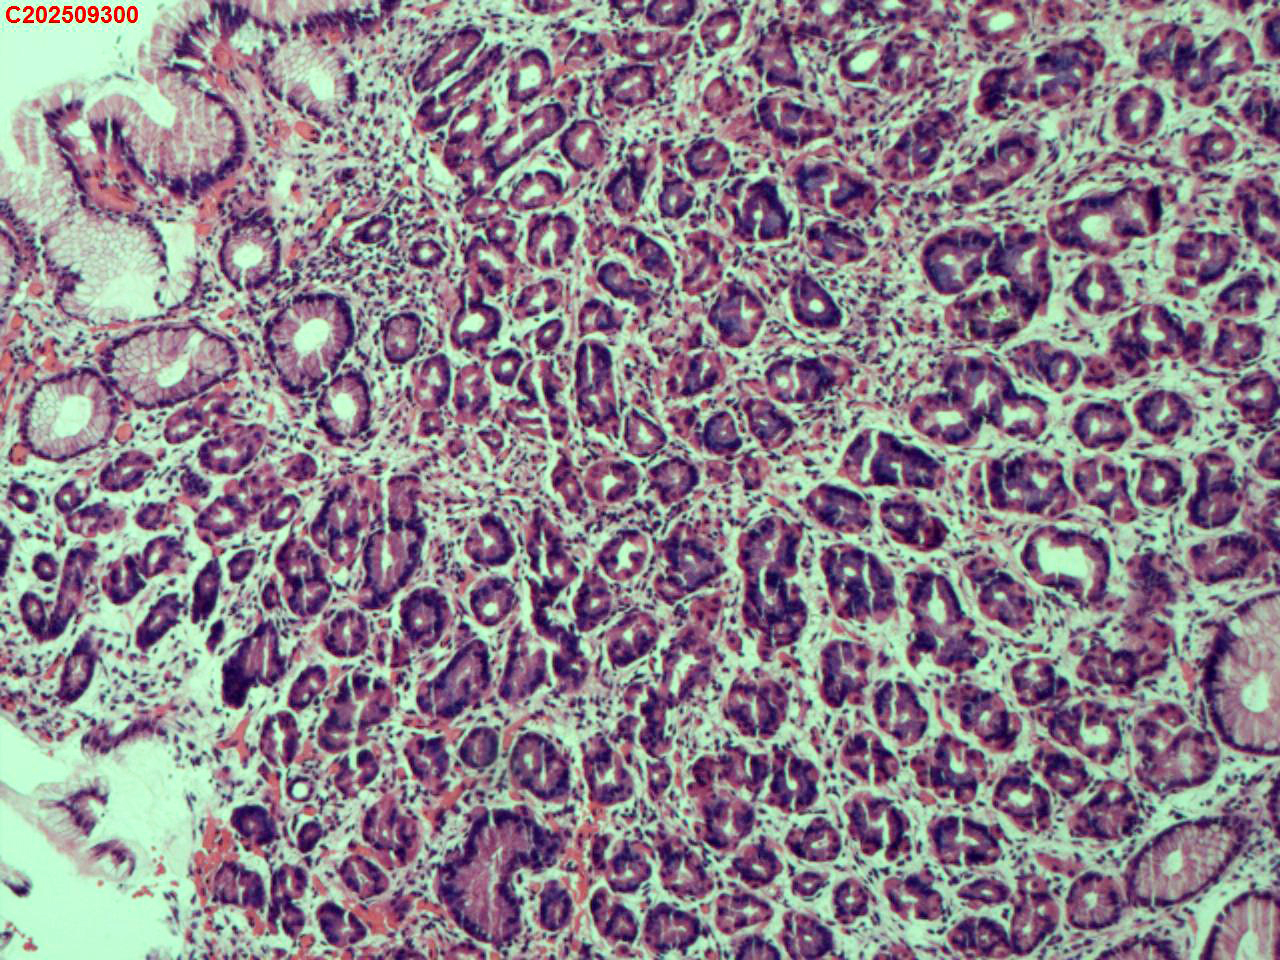

胃底粘膜

性别

女

年龄

44岁

临床诊断

胃息肉

一般病史

体检

标本名称

大体所见

胃底:可见一枚直径约2mm的半球形息肉。

增生性息肉